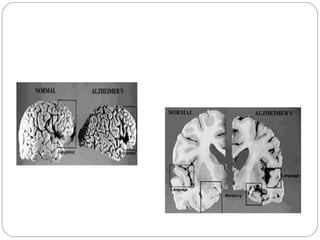

Cérebro Normal X Doença de Alzheimer

Definição Caracteriza-se clinicamente pelaperda progressiva da memória. O cérebro de um paciente com o Mal de Alzheimer, quando visto em necrópsia, apresenta uma atrofia generalizada , com perda neuronal específica em certas áreas do hipocampo mas também em regiões parieto-occipitais e frontais.

Cérebro Normal XDoença de Alzheimer